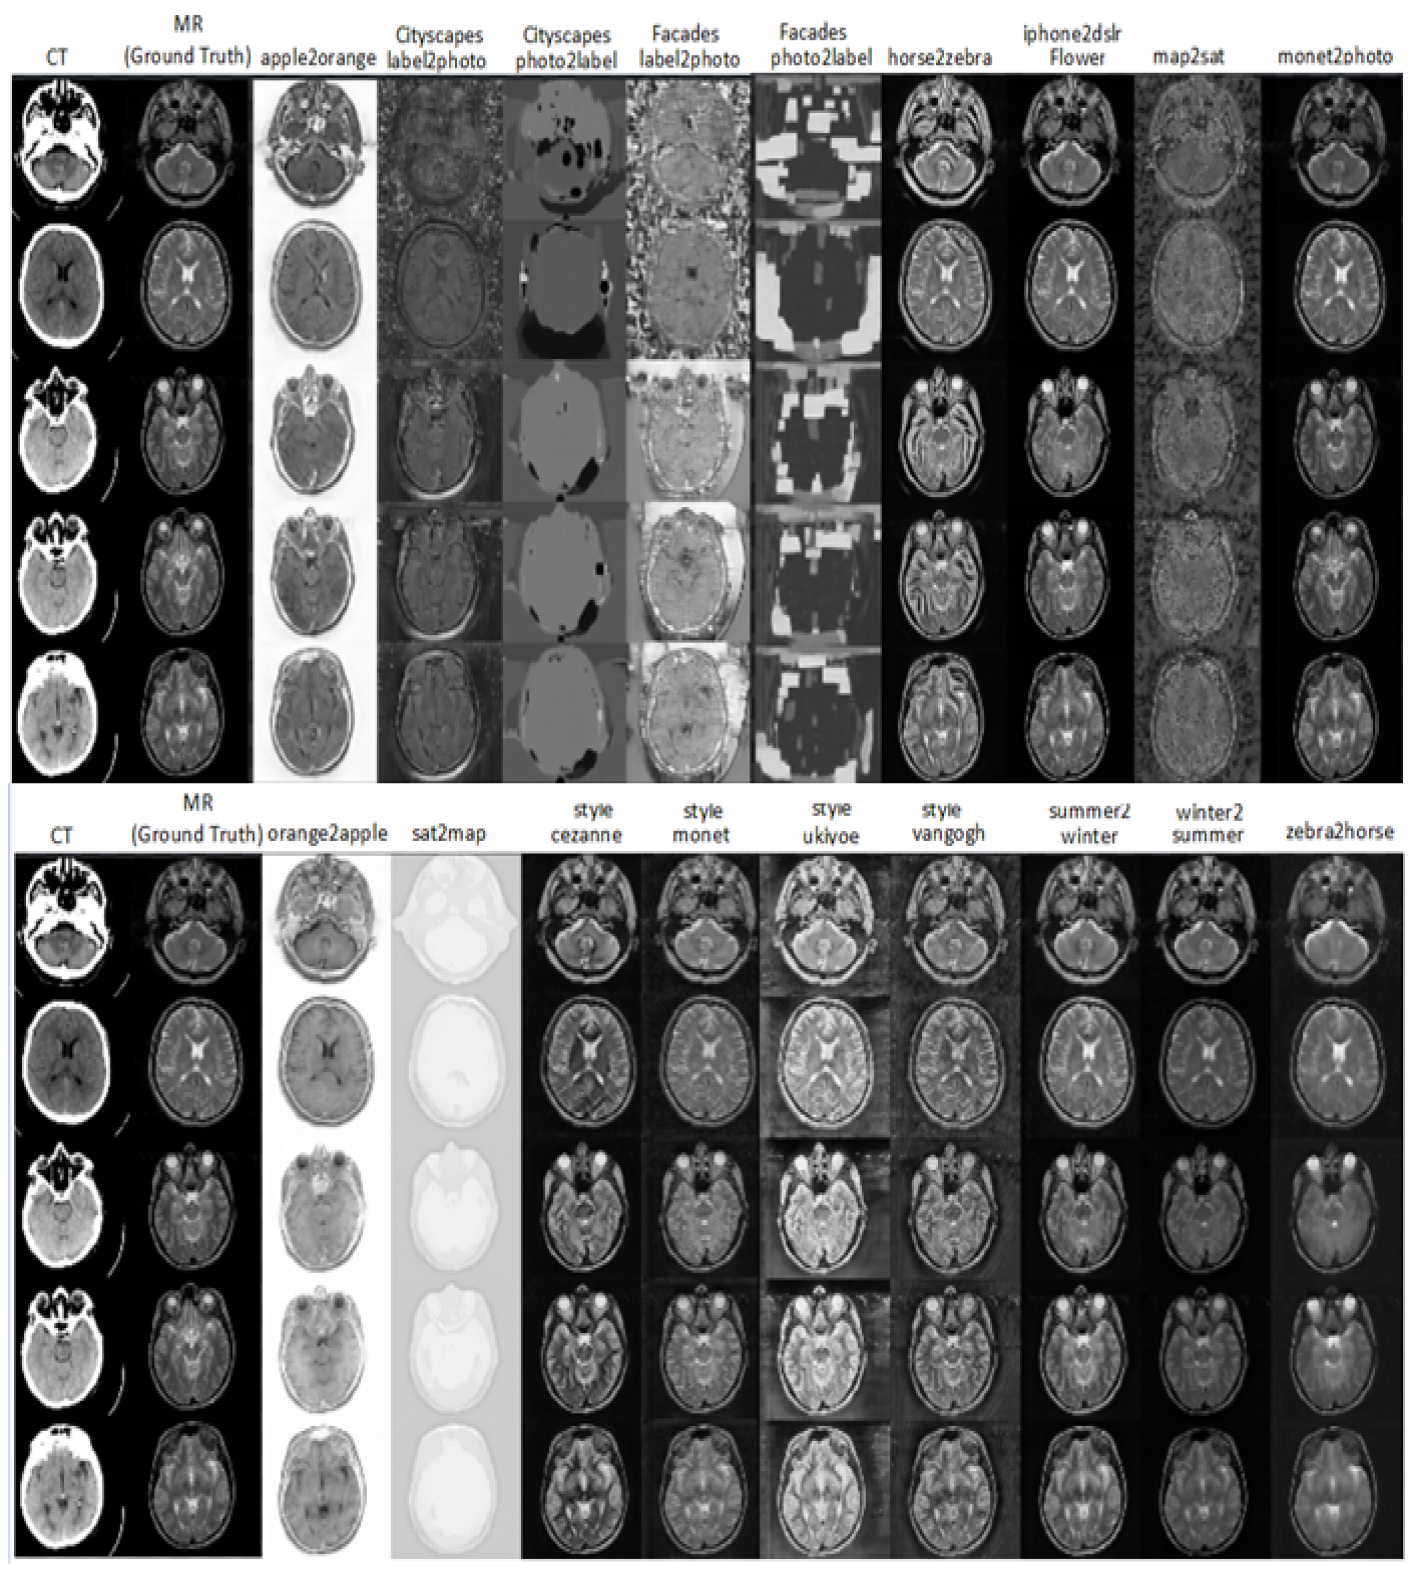

In image synthesis tasks, the evaluation of generated images is crucial to assessing the quality of the model’s output. The commonly used PSNR metric, which calculates the mean square error between the original and generated images, has limitations as it does not always correlate with human visual perception. Therefore, additional metrics such as SSIM, UQI, and VIF have been proposed to overcome these limitations. In this work, the performance of the model is evaluated using these metrics on both the paired and unpaired datasets. The experiments compared the bidirectional MR-CT synthesis using 18 pre-trained non-medical models, and the iphone2dslr_flower model outperformed the others, resulting in the best score across most of the chosen metrics, with low standard deviation values indicating the stability of the results. Figures 5 and 6 illustrate Bidirectional MR-CT Translation, using a pre-trained model.

Figure 5: Output results of Magnetic Resonance to Computed Tomography (MR-CT) image translation from different generic pre-trained models.

Figure 6: Output results of Computed Tomography to Magnetic Resonance (CT-MR) image translation from different generic pre-trained models.

In Fig. 5, a comprehensive analysis of the outcomes reveals a consistent correlation with the findings presented in Fig. 3, which showcases the diverse results obtained from the pre-trained model. Notably, a subset of these models, including facades photo2label and facades label2photo, exhibited erroneous outcomes attributed to their primary specialization in region identification and labeling. Moreover, the sat2map variant also demonstrated significantly divergent results from the desired outcomes. As a result of our meticulous examination, we arrive at the conclusion that the crucial determinant for achieving satisfactory results lies in the judicious selection of a pre-trained model that is specifically tailored to a dataset possessing properties closely resembling the new images used for the model’s training. This underscores the pivotal role played by appropriate model selection in ensuring the successful training of the model. The iphone2dslr_flower model stands out as the premier pre-trained non-medical model for image translation, and it has also exhibited exceptional capabilities in the medical field, particularly in translating MRI images into CT scans, achieving top scores in all four evaluation scales. This pre-trained generative model was trained on a vast image dataset, the iphone2dslr_flower dataset, which proves to be an ideal choice for transfer learning in photomontage tasks. This dataset comprises images of flowers captured by both iPhone and DSLR cameras, allowing the training of models capable of generating high-resolution flower images that closely resemble the quality of those taken with a DSLR camera. The model’s training involved a diverse range of images, including flowers that share visual similarities with certain structures in the human body, such as blood vessels [24]. Additionally, some flower types exhibit compact corals with intricate convoluted surfaces reminiscent of brain structures, making this dataset especially valuable for models aiming to reproduce the intricate details and textures found in these floral specimens. The petals displayed a striking resemblance to the inner tissues of the brain, exhibiting a repeating pattern that mirrors the distinctive torsions and folds present in cerebral structures [21]. This intriguing similarity between the model’s results and brain anatomy highlights the potential of this approach to capture complex biological patterns and structures. The model’s ability to capture such fine details indicates a close match between the training data and brain features, ultimately contributing to its exceptional performance in the realm of brain image analysis. Figure 8 showcases some of the flowers utilized in the iphone2dslr_flower dataset, further illustrating the dataset’s diversity and relevance for the model’s training. and Figure 9 Resemblance between Brain Images and iPhone Data. The images showcase striking similarities between brain structures and the data generated by the iPhone model. The intricate patterns and textures found in certain types of flowers captured by the iPhone camera demonstrate a captivating resemblance to brain tissues [14], highlighting the potential of the model in capturing complex biological structures.